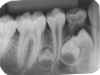

ANOMALIAS

1